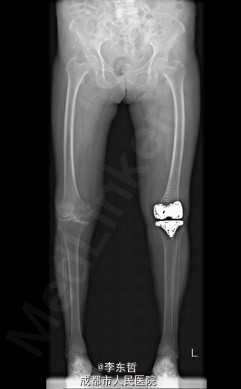

患者女,74岁,因“双膝疼痛20年,加重伴行走困难8年”入院。患者诉20年前开始出现双膝关节疼痛,负重行走、下楼时疼痛加重,休息后可缓解,尚可下蹲。自行购买止痛药口服,关节腔内注射玻璃酸钠、理疗等处理,疼痛时有缓解。但症状反复发作。8年前疼痛加重且行走困难,扶拐行走仅能坚持约10余米,上下楼梯艰难,下蹲不能,以左侧为重。遂来院就诊。

查体:跛行步态,双膝关节屈曲内翻畸形,双膝内侧间隙压痛,双膝髌股关节间隙压痛,左膝伸-20°,屈110°内翻10°。右膝伸-20°,屈110°内翻10°,双膝屈伸活动时髌骨下摩擦感(+)。 辅助检查:X片示双侧髌股关节内侧间室变窄,关节边缘骨赘增生,软骨下骨硬化。

入院诊断:1、左膝骨关节炎伴屈曲内翻畸形; 2、右膝骨关节炎伴屈曲内翻畸形; 诊疗计划:1、向患者及家属交待病情及注意事项。2、向上级医生汇报患者病情。3、完善相关术前检查;4、择期手术。